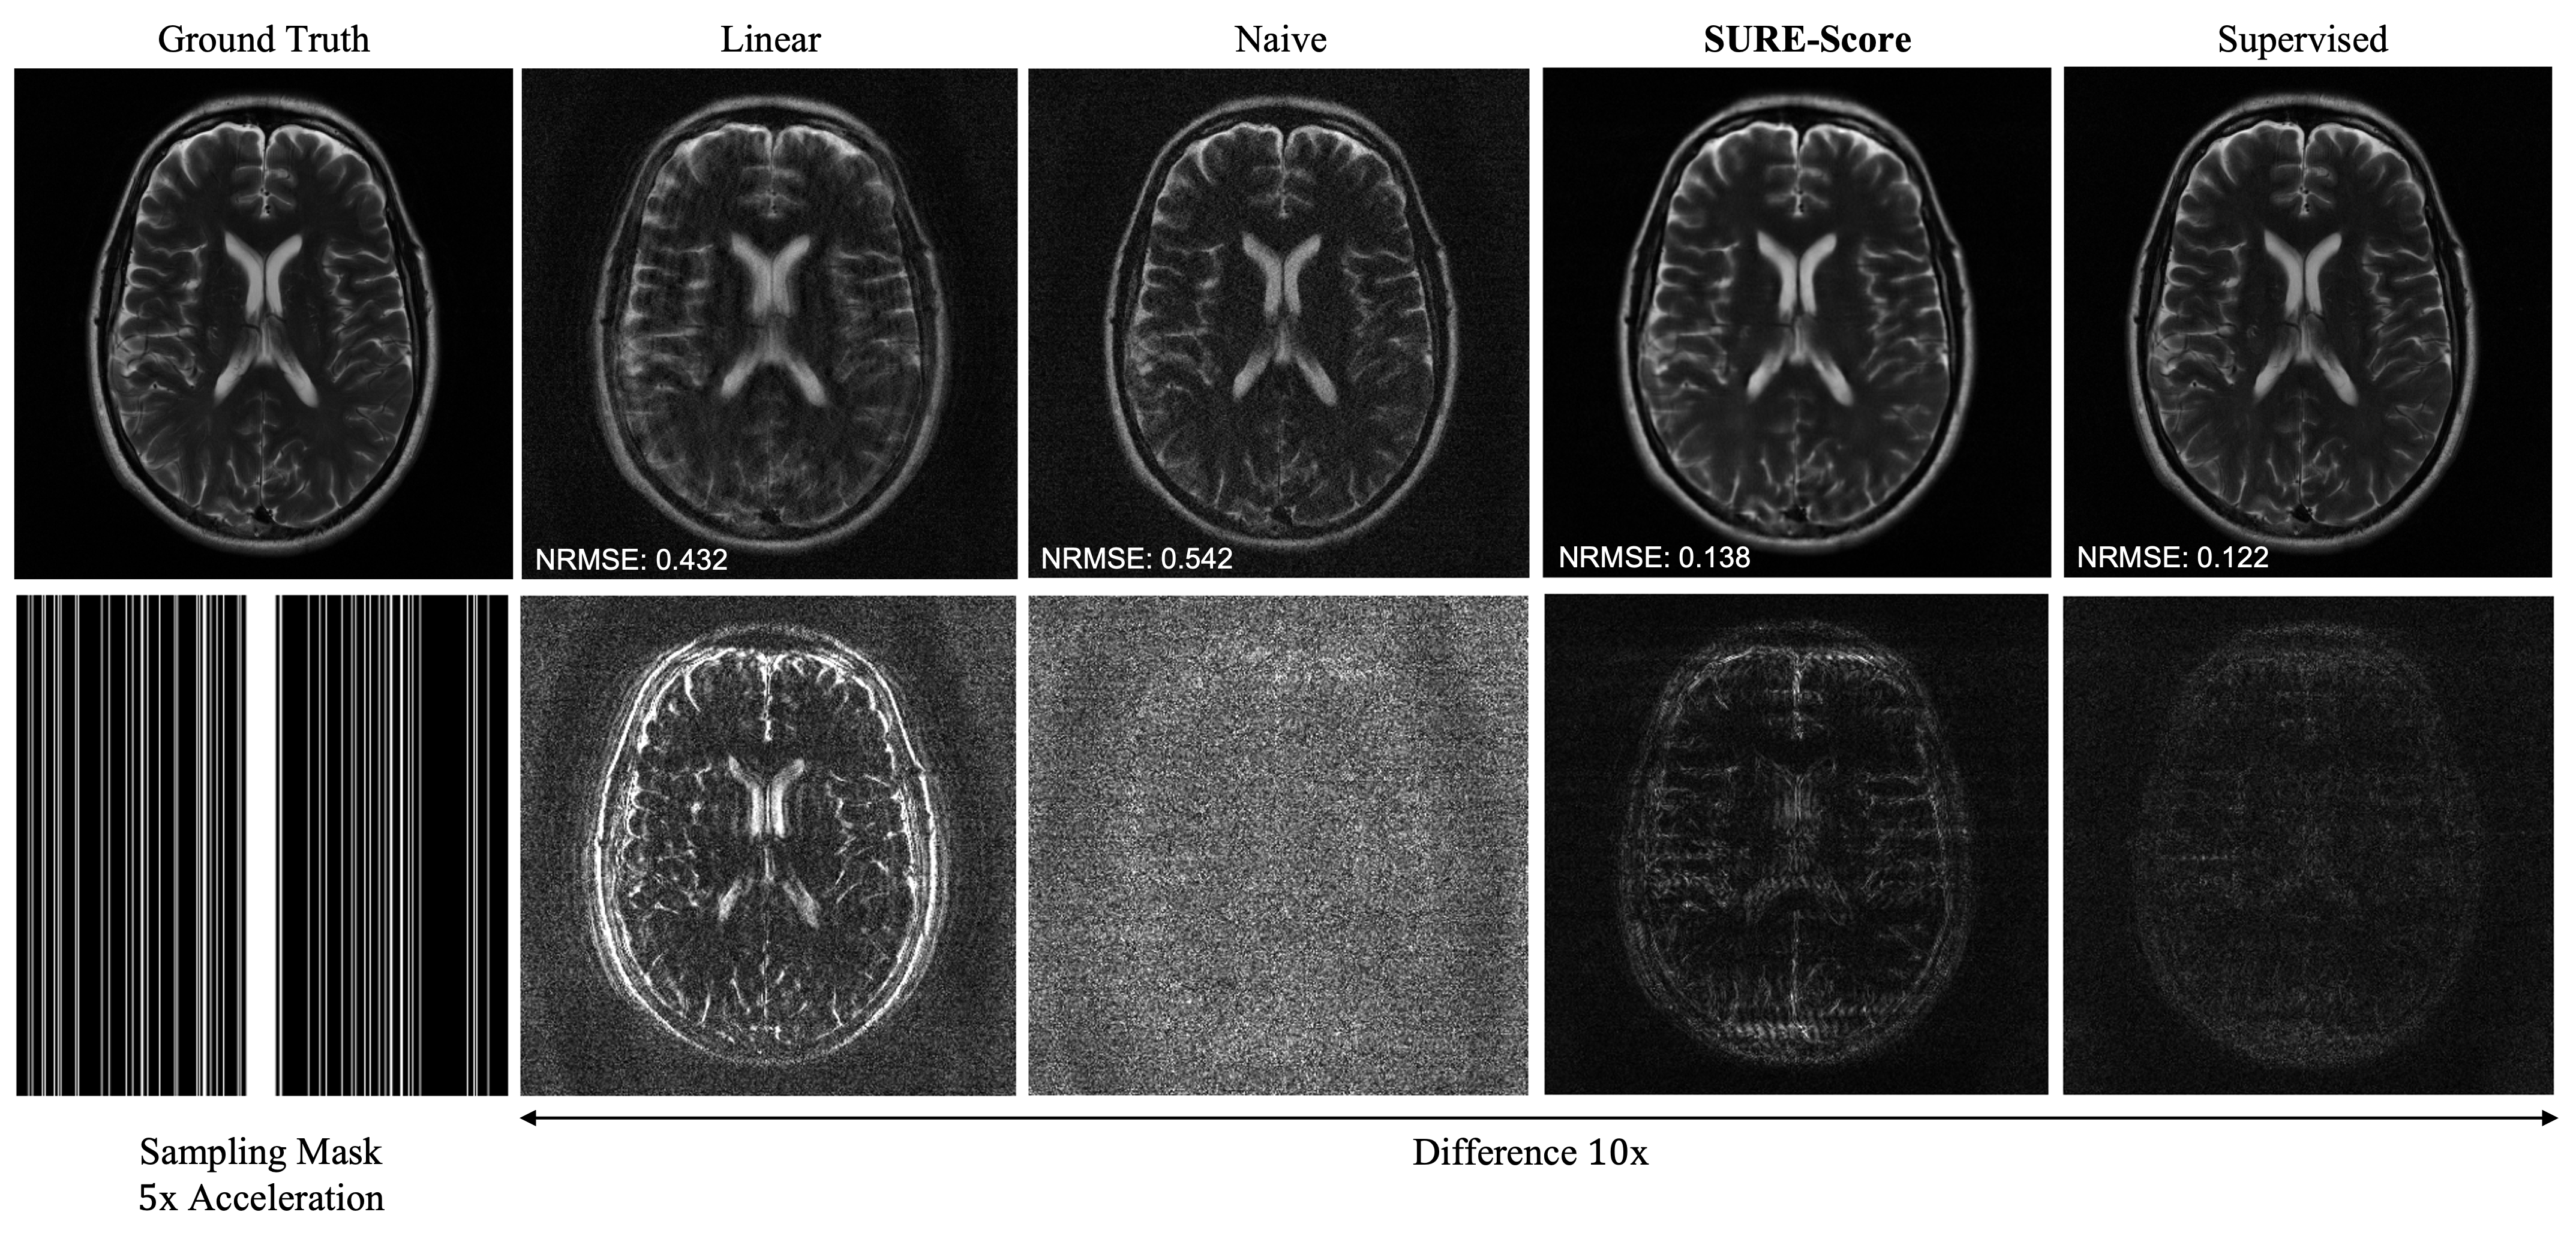

Table II displays reconstruction NRMSE (mean and standard deviation) over a validation set of slices. We compare linear reconstruction, naive training, supervised training, and SURE-Score. We observe similar trends as in our MIMO experiments. Figure 4 compares example reconstructions after training with noisy data at . Naive training leads to noise amplification, while SURE-Score qualitatively and quantitatively improves over this result.

We use annealed Langevin dynamics as previously described in (7). We simulate an acceleration factor of five using a vertical sampling mask with fully sampled central k-space and uniform random sub-sampling elsewhere. We assume high SNR and set during inference.

IV-C2 Posterior Reconstruction